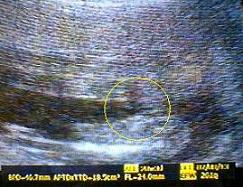

BPD(児頭大横径)=46.7o

FL(大腿骨長)=24.0o

APTD(腹部前後径)=47.0o

TTD(腹部横径)=39.5o

推定体重=261g

かなり大きくなりました!

ちょうど1週間分くらい大きいみたいw

左上が頭、右上が顔、左下がおなかまわり、右下が足の写真。

性別をみてもらったけど写真は撮ってもらえなかったのでビデオ再生して撮影。

今日みた感じだと女の子のようです^^